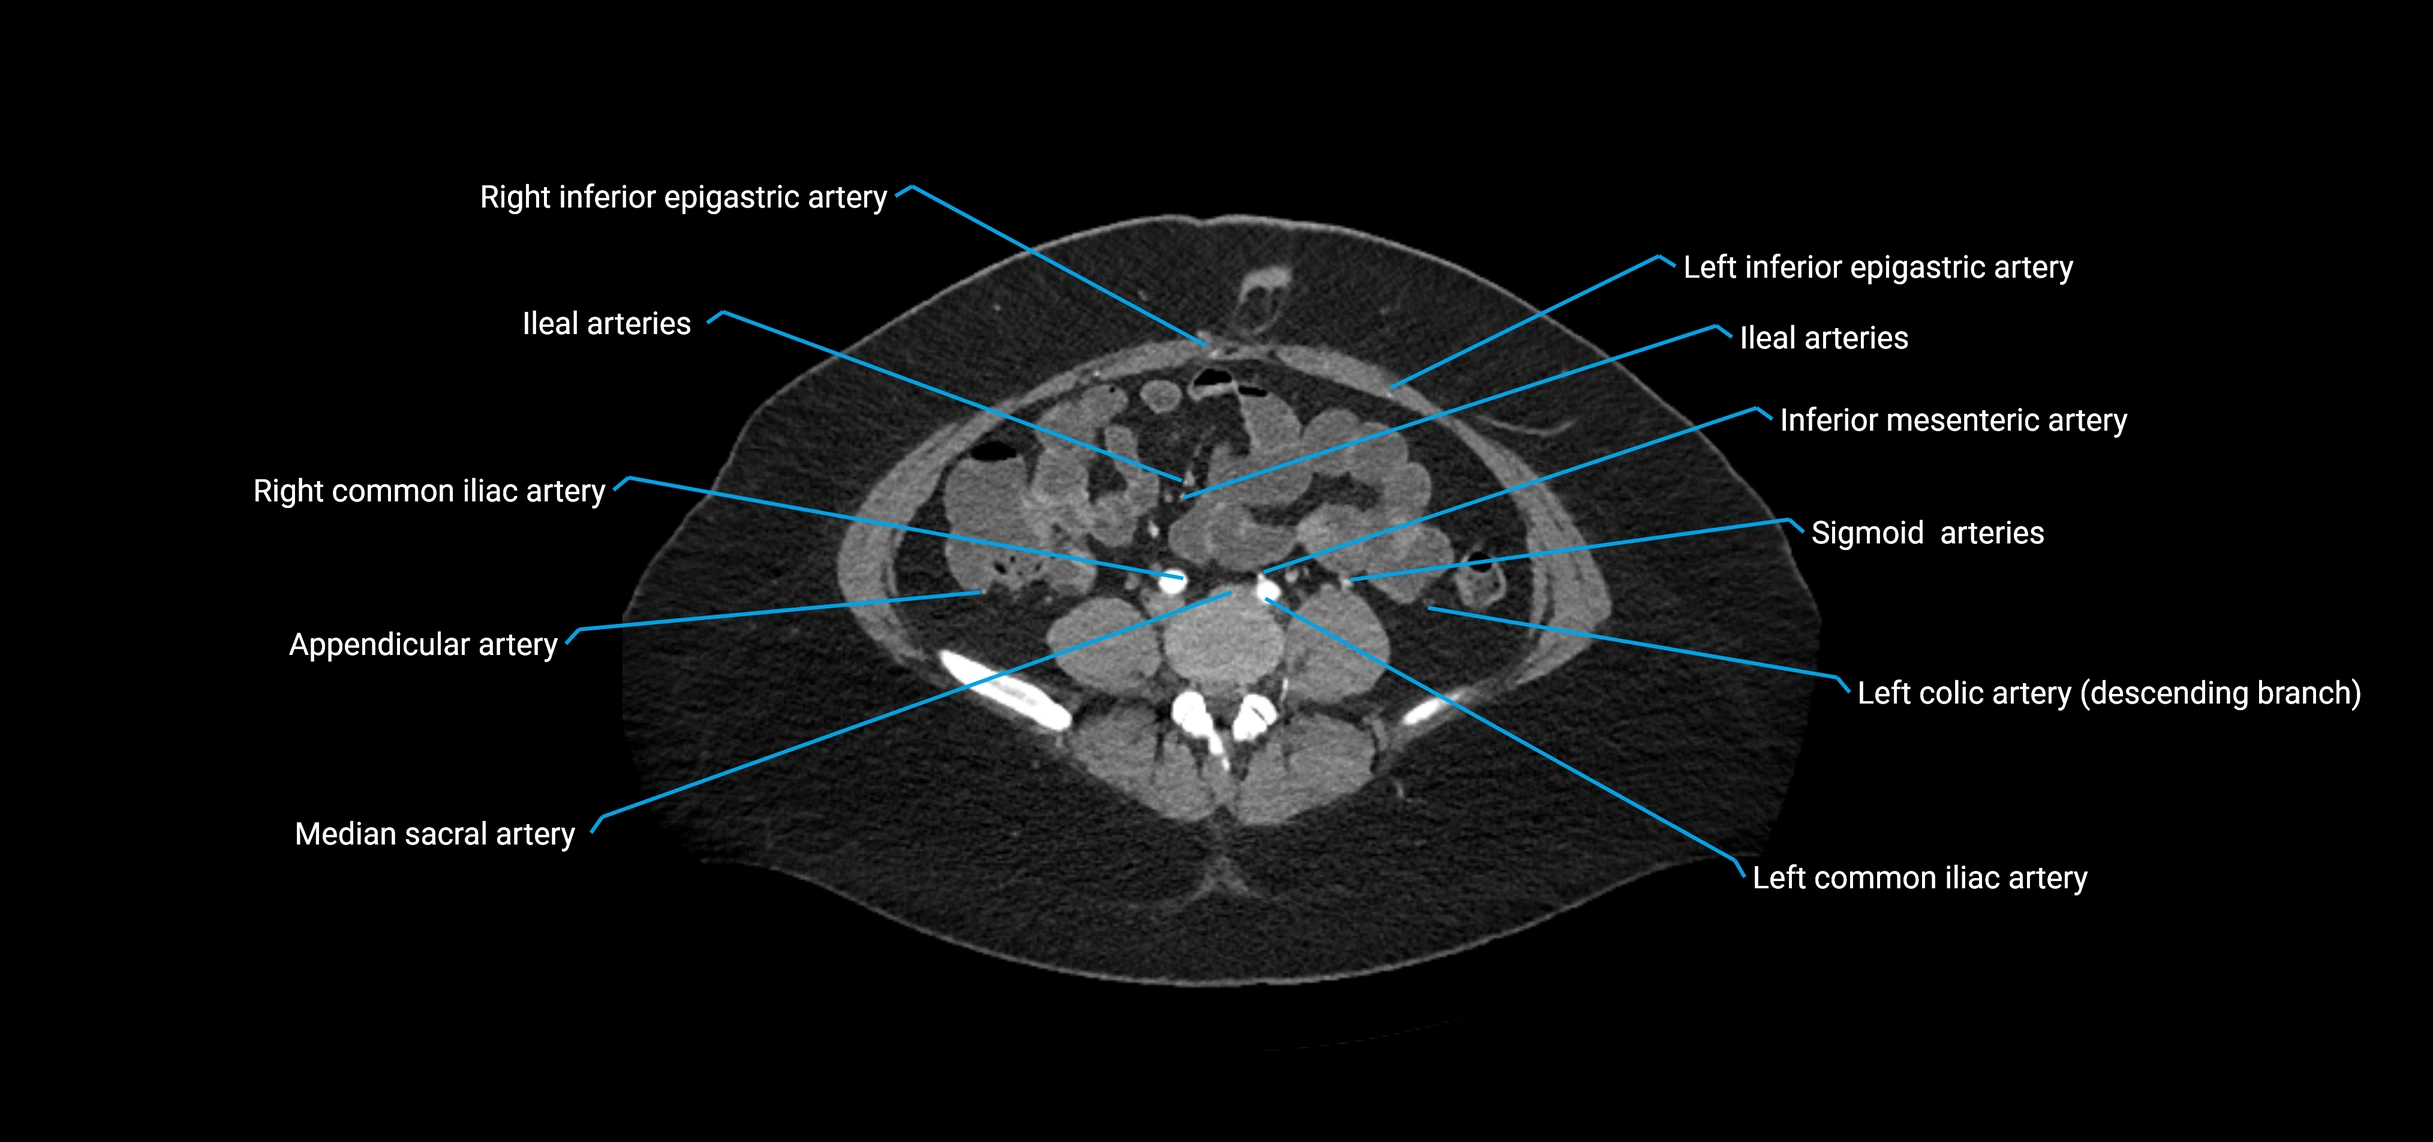

Contrast-enhanced CT (CTA):

• Gold standard for abdominal aortic imaging

• Provides excellent detail of lumen, wall, aneurysm, thrombus, and branch vessels

• Multiplanar and 3D reconstructions help in aneurysm measurement, stent graft planning, and dissection evaluation

• Detects acute rupture, traumatic injury, or occlusion with high sensitivity